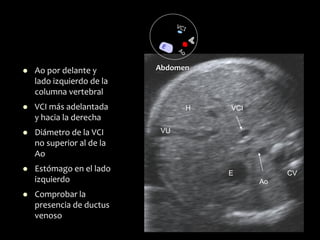

⚫ Ao por delante y

lado izquierdo de la

columna vertebral

⚫ VCI más adelantada

y hacia la derecha

⚫ Diámetro de la VCI

no superior al de la

Ao

⚫ Estómago en el lado

izquierdo

⚫ Comprobar la

presencia de ductus

venoso

Abdomen